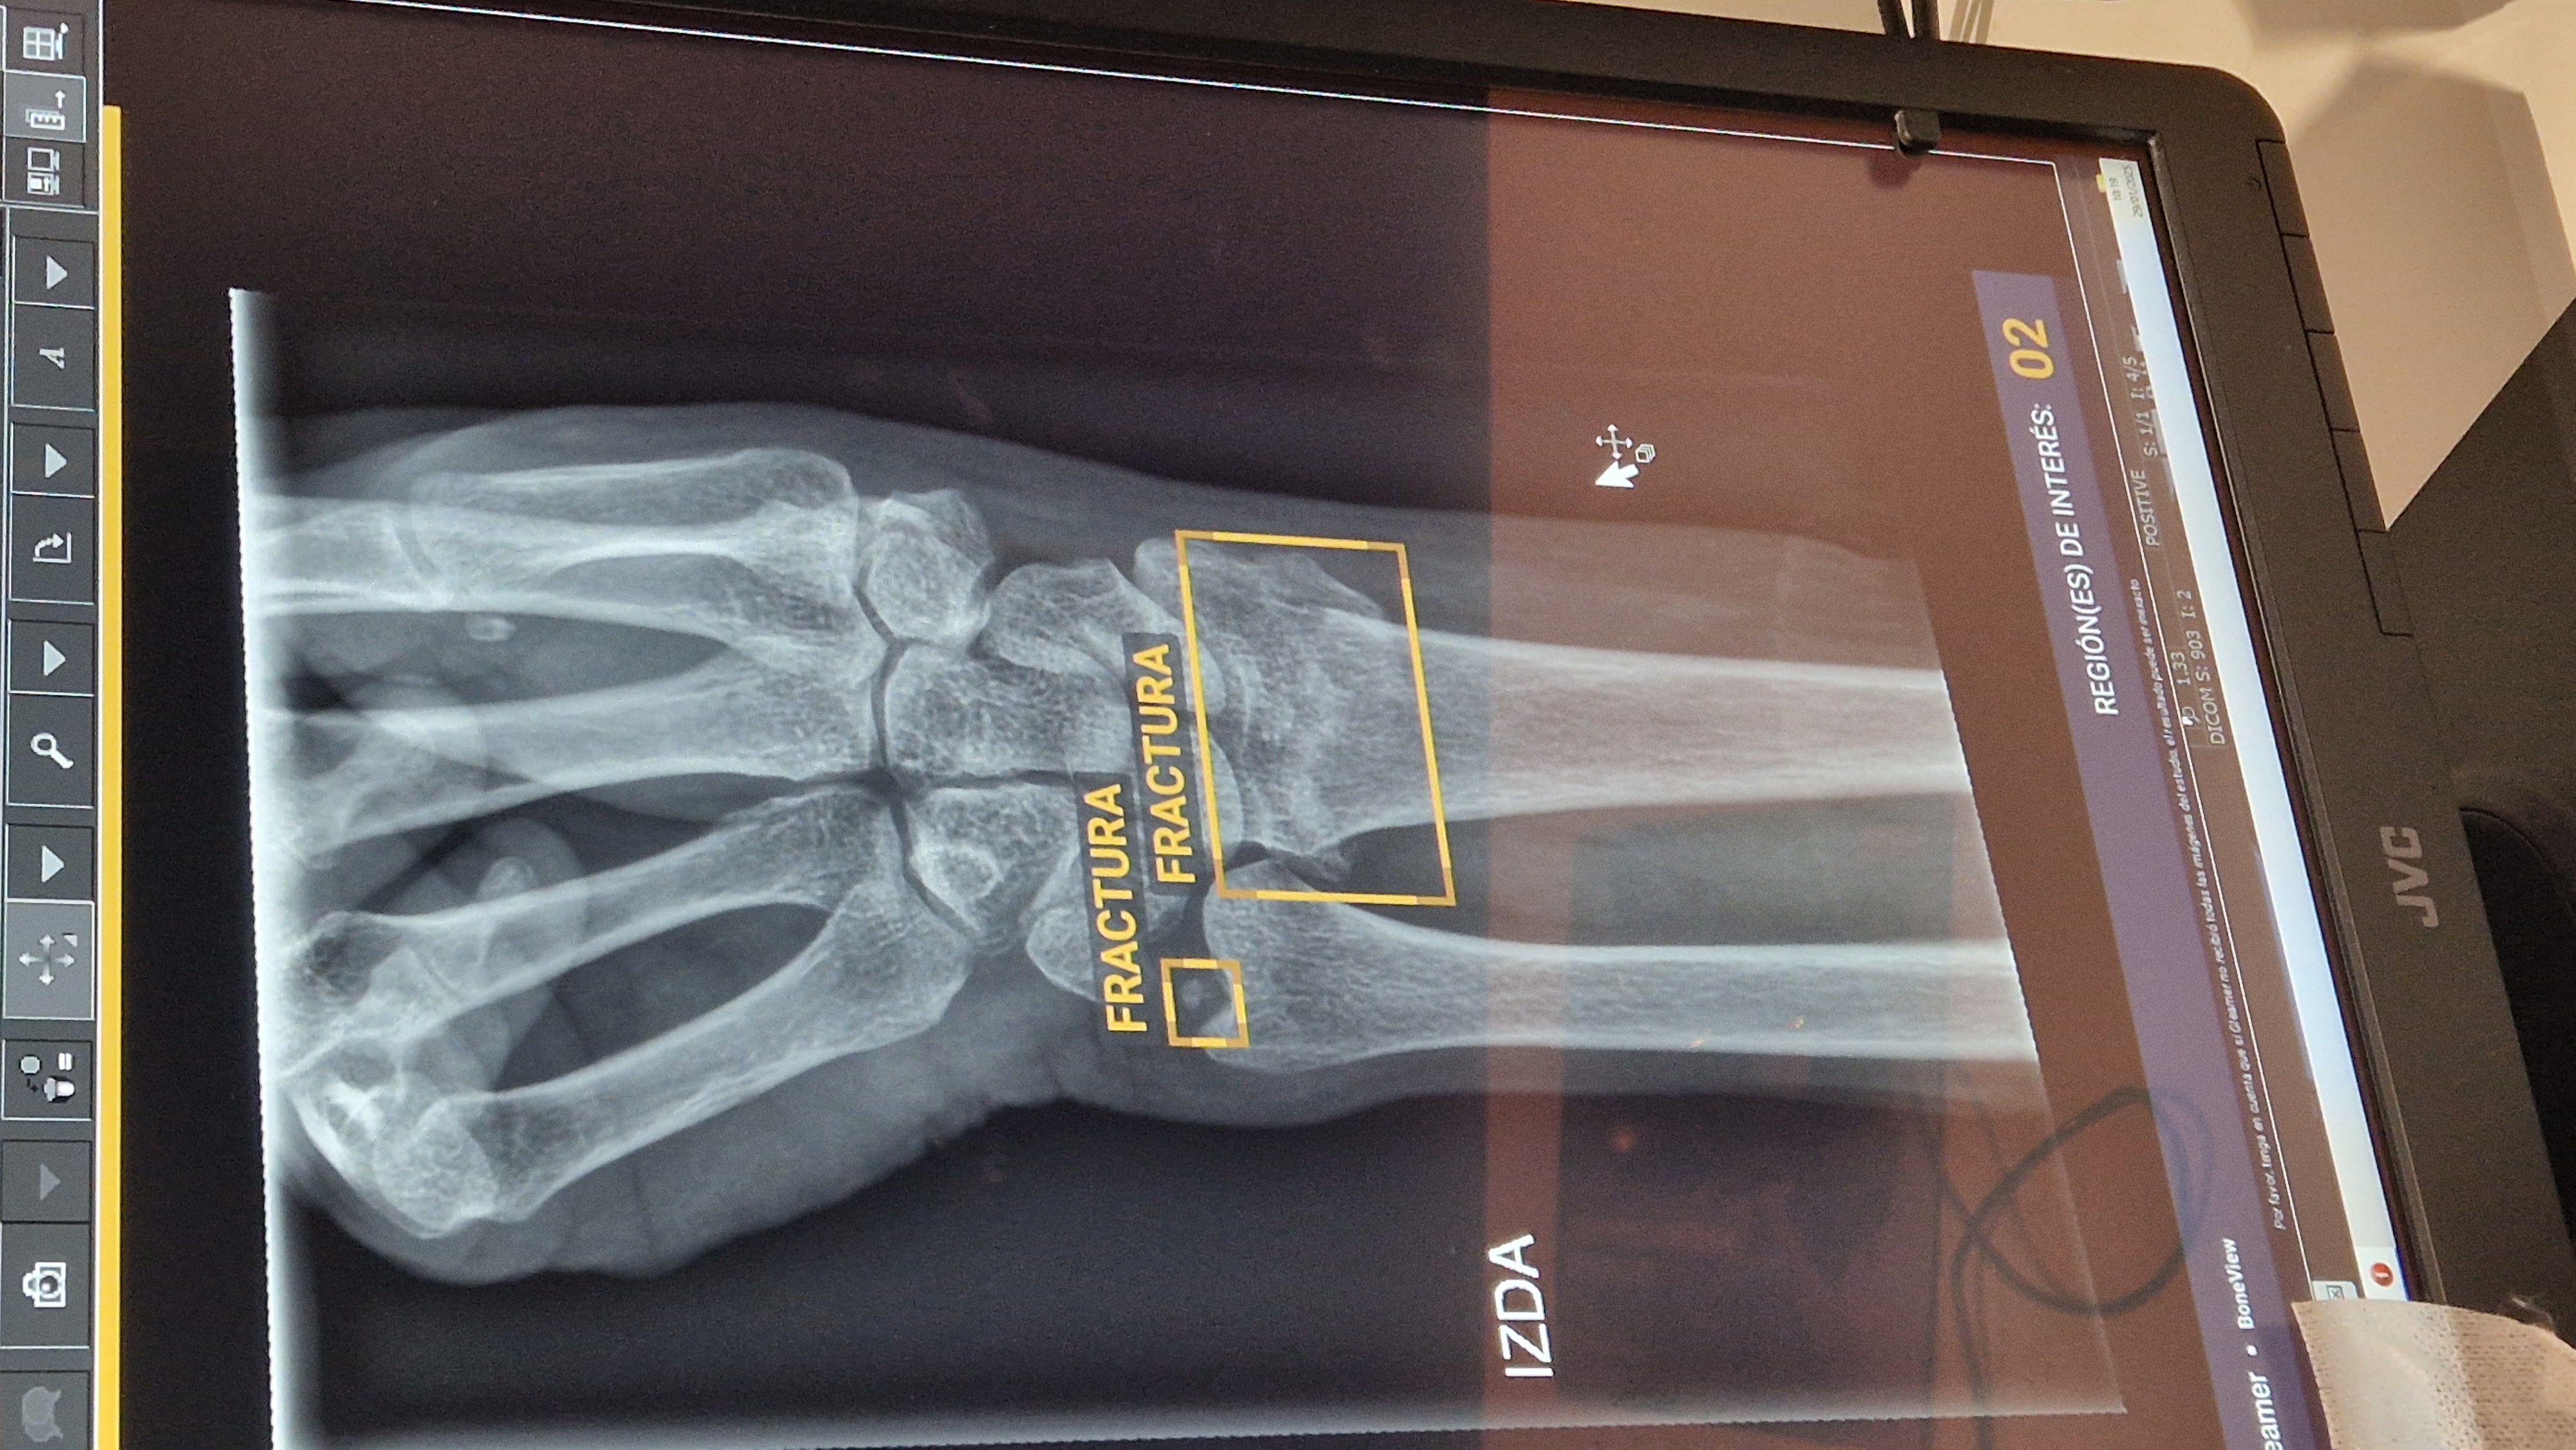

El primero de ellos, conocido como BoneView, ayuda a la toma de decisiones en el diagnóstico de fracturas. Tras la realización de una radiografía, la imagen se envía al sistema de archivo y comunicación de imágenes –conocido como PACS, donde se anonimiza y se devuelve analizada por la inteligencia artificial. En escasos segundos, se genera una segunda imagen que proporciona una evaluación de la presencia de fracturas, luxaciones o lesiones óseas y las localiza, mostrándolas directamente en la pantalla.

El examen se divide en tres categorías: presencia de fractura, sospecha de fractura o ausencia de fractura. Esa segunda imagen se almacena nuevamente en el PACS, junto con la radiografía inicial, y aporta toda la información para el diagnóstico.

Cada radiografía muestra un recuadro alrededor de la zona de interés para facilitar que se fije la atención en esa área. Este procedimiento permite incrementar el rendimiento diagnóstico y la seguridad, ya que tiene un valor predictivo del 99% para descartar patologías.